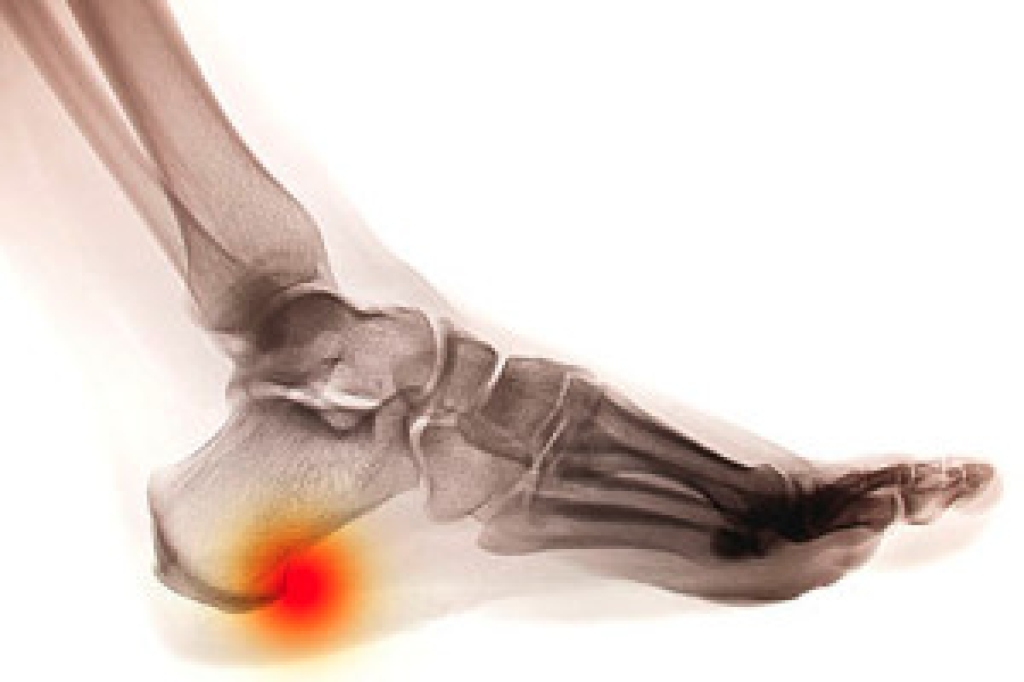

The Achilles tendon is a tendon that connects the lower leg muscles and calf to the heel of the foot. It is the strongest tendon in the human body and is essential for making movement possible. Because this tendon is such an integral part of the body, any injuries to it can create immense difficulties and should immediately be presented to a doctor.

There are various types of injuries that can affect the Achilles tendon. The two most common injuries are Achilles tendinitis and ruptures of the tendon.

- Extreme pain and swelling in the foot